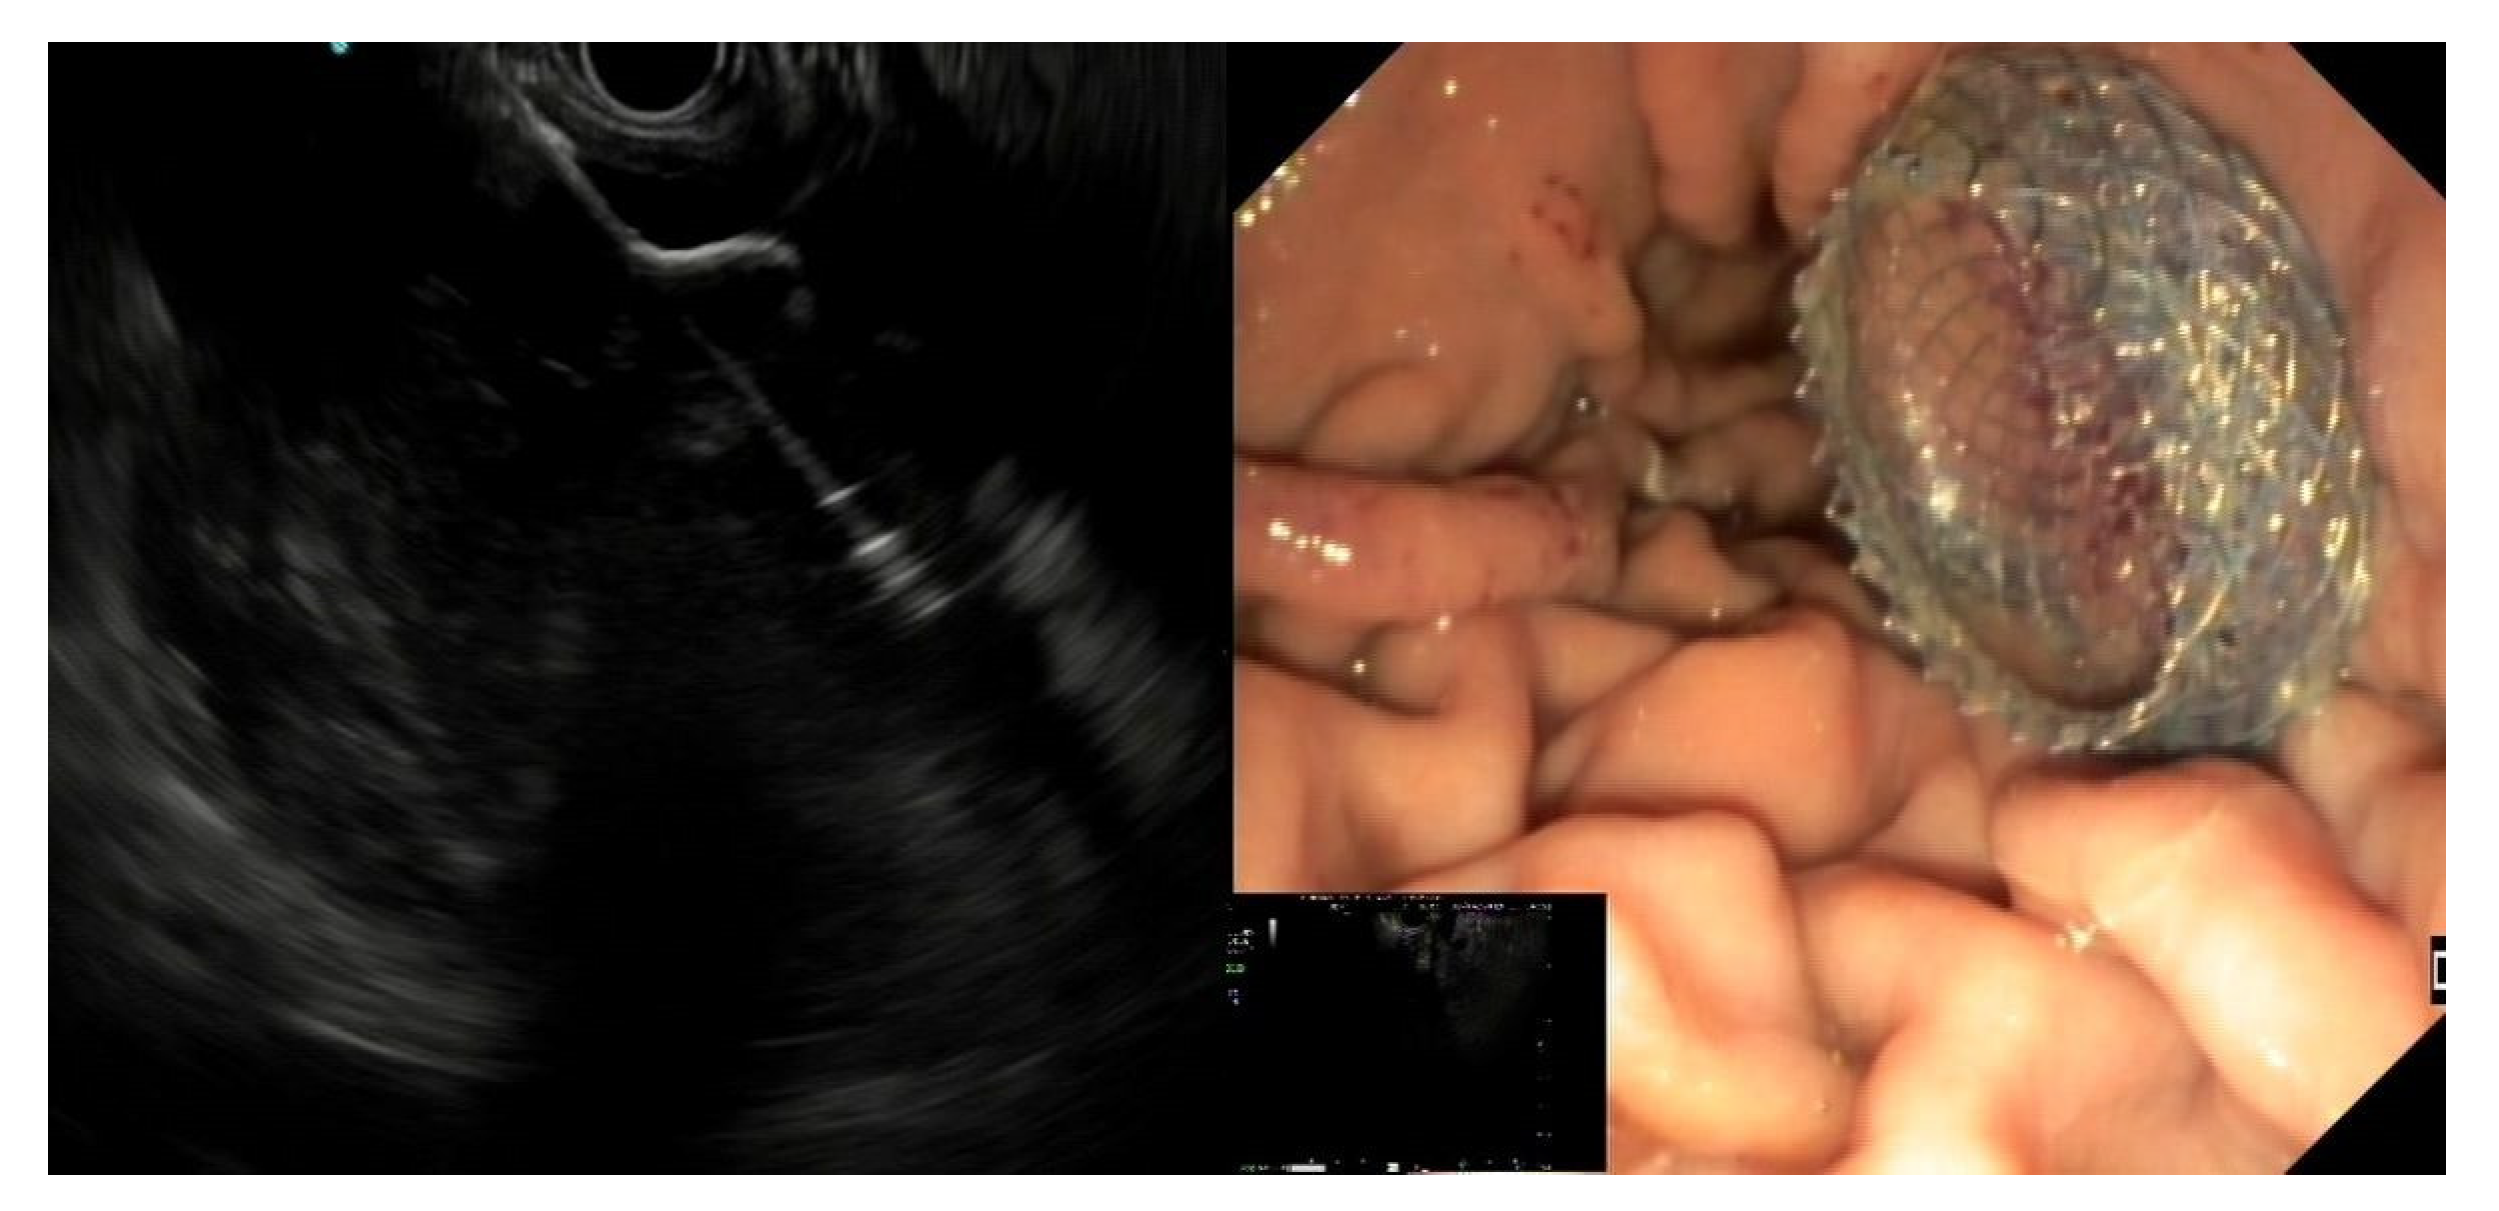

- EC-LAMS: the deployment catheter is positioned on the selected point on the gastric/duodenal wall. The activation of the electro-cautery tip allows direct passage of the catheter into the collection under EUS guidance. The distal flange of the LAMS is deployed, and the next steps are the same as the LAMS (Figure 3) [50].